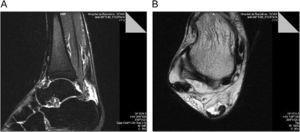

DESCRIPCIÓ DEL CASJugador de bàsquet professional que durant la temporada 2008–09 pateix en un entrenament una estrebada muscular a la cama dreta durant una acció defensiva, quan passava dun estirament de la cama per frenar el cos cap enrere, a una flexió plantar brusca per tirar al cos endavant . Durant les primeres 48h es fa tractament tipus RICE (rest, ice, compression, elevation) i se li va permetre caminar, si bé ho fa amb dificultat. Es realitza un primer estudi ecogràfic ales 12h que determina una lesió del m. bessó intern amb un petit hematoma mio-fascial. Davant la sospita clínica i ecogràfica duna lesió del m. soli aconsellem un estudi mitjançant ressonància magnètica (RM) a les 24h de produir-se la lesió . Lestudi per RM, realitzada mitjançant sistema de 1,5T (Magnetom Essenza, Siemens Healthcare), és informada de lesió tipus tennis leg (figura 1).

Figura 1. a) Imatge axial potenciada en T2 obtinguda en la porció distal del bessó intern; mostra líquid dins de la unió mio-fascial entre el m. Soli i el m. Bessó intern i en la unió mio-tendinosa distal del bessó intern. També saprecien focus de hipersenyal dins del bessó intern, que presenta una discreta retracció i del m. Soli. b) imatge coronal stir dels bessons que mostra líquid en la unió miotendinosa distal del m. Bessó intern i edema intramuscular del m. Soli i m. Bessó intern.